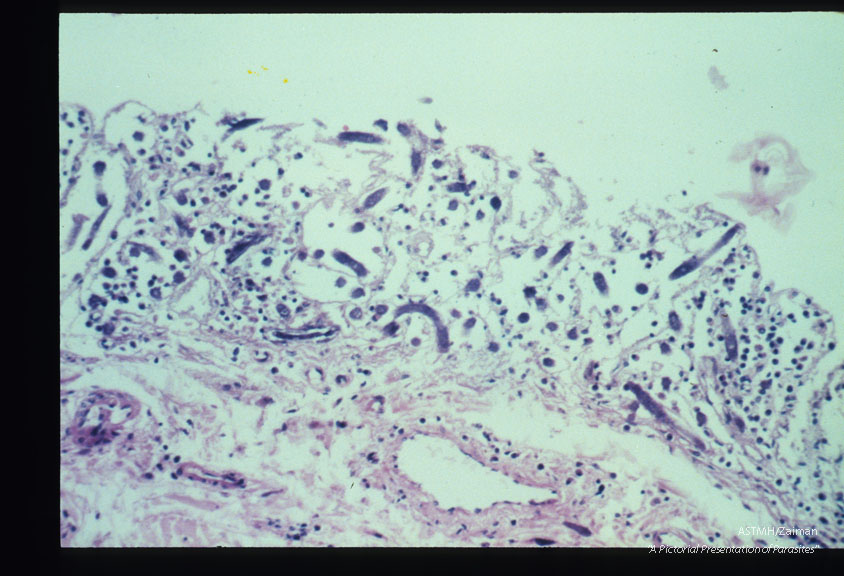

Hyperinfection in the colon of an immunosuppressed patient.

Strongyloides stercoralis

Description: Hyperinfection in the colon of an immunosuppressed patient.